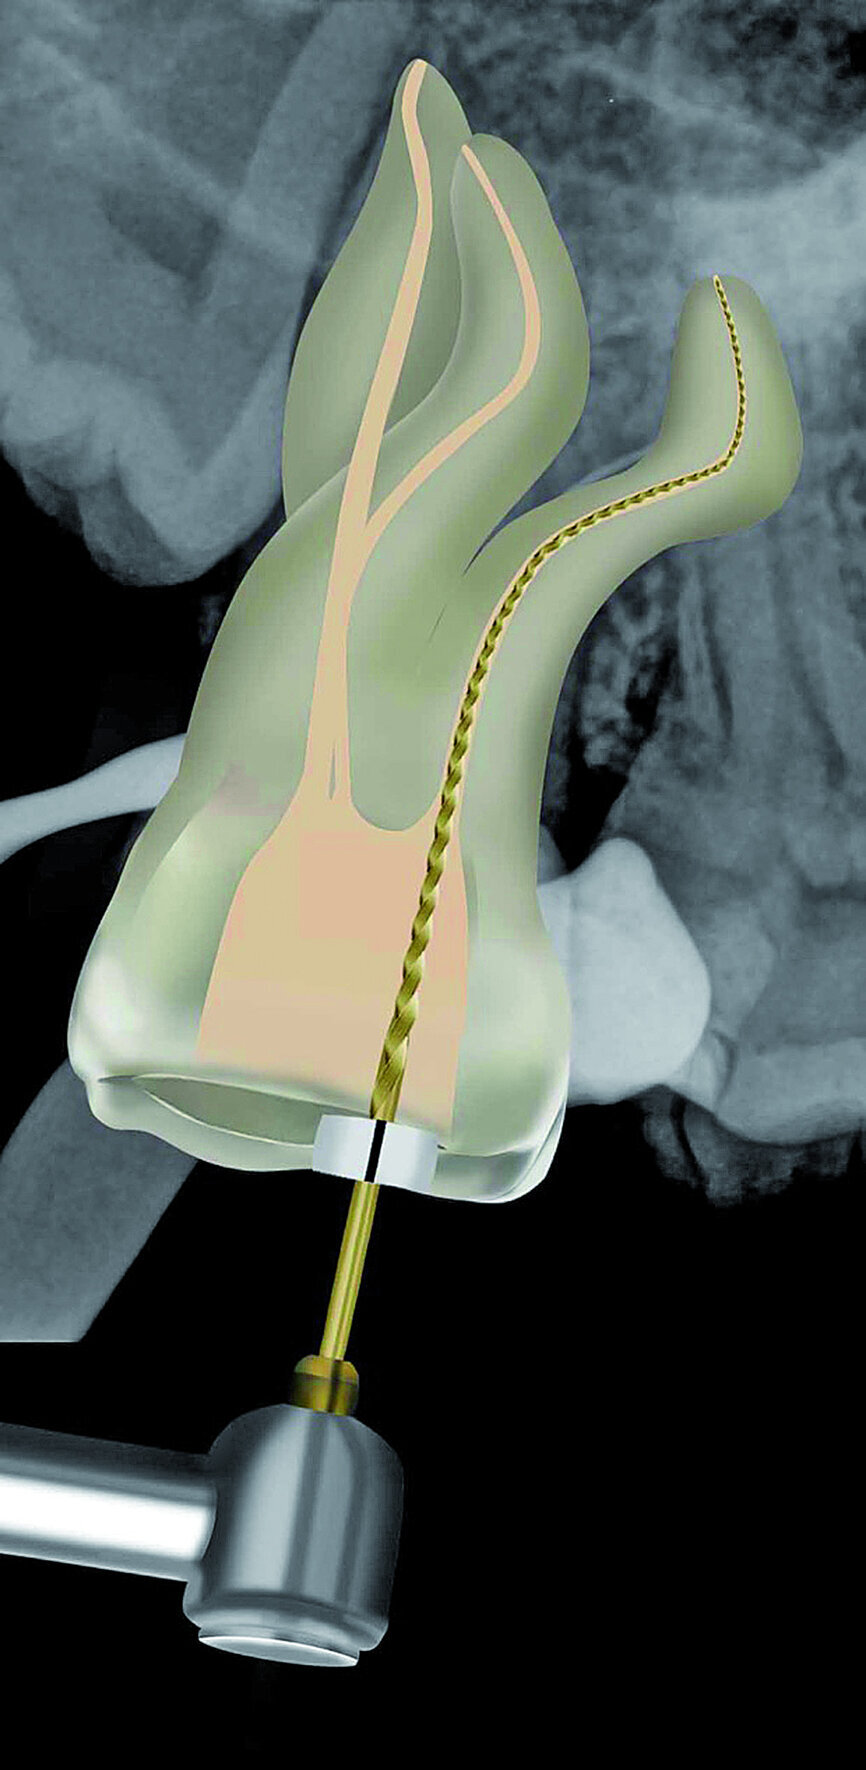

Fig. 23: A ProGlider was used in a rotary motion to expand the glide path in the palatal root canal.

The pulp chamber was filled with Glyde (Dentsply Sirona) before the canals were carefully negotiated to full working using pre-curved size 08 K-Files (Fig. 19). Working length measurements obtained from an electronic apex locator reading corresponded with the lengths obtained from the 3D Endo Software. These measurements were also confirmed radiographically (Fig. 20). A reproducible glide path was prepared in each root canal system with the size 08 K-File in an M4 Reciprocating handpiece (Sybron Endo; Fig. 21), followed by making a size 10 K-File ‘super loose’ (Fig. 22). A ProGlider (Dentsply Sirona) was used in a rotary motion to expand the glide path in the palatal root canal (Fig. 23). Considering the sharp and severe curvatures in the two buccal canals, it was decided to convert the ProGlider instrument into a manual file to expand the glide path in these tortuous canals with more safety (Fig. 24). The manually adapted ProGlider was used in a balanced force motion up to working length. In addition, to create more safety during the canal preparation of the two challenging buccal root canals, it was also decided to use the reciprocating WaveOne Gold Glider (Dentsply Sirona; Fig. 25), after the ProGlider instrument to further expand the glide paths. The WaveOne Gold Glider was used in 4–8 backstroke brushing motions from working length, in the two buccal root canal systems.

The ProGlider, a single file rotary glide path instrument was the first instrument used to expand the glide paths. This file is manufactured from M-wire NiTi alloy that shows more flexibility and resistance to cyclic fatigue compared to conventional NiTi alloy. It has a semi-active tip, size ISO 016 (D0) with a 2 % taper that progressively increases up to 8 % (D14; Fig. 29). The cross section of the ProGlider instrument is square and the file is used in a continuous rotary motion at 300 rpm and a torque setting of 2–4 Ncm. [14] Considering the severe curvatures in different planes of the buccal root canal systems, the ProGlider instrument was first used in a manual mode up to working length in these two canals. It was also then decided to further expand the glide path in these canals by using the WaveOne Gold Glider, also a single, reciprocating glide path file designed for glide path enlargement. Here, a second glide path instrument was used because the cutting envelope of the WaveOne Gold Glider is more than the ProGlider instrument (Fig. 30). The rationale for this double file approach for glide path expansion was to enhance safety for the preparation files that followed.